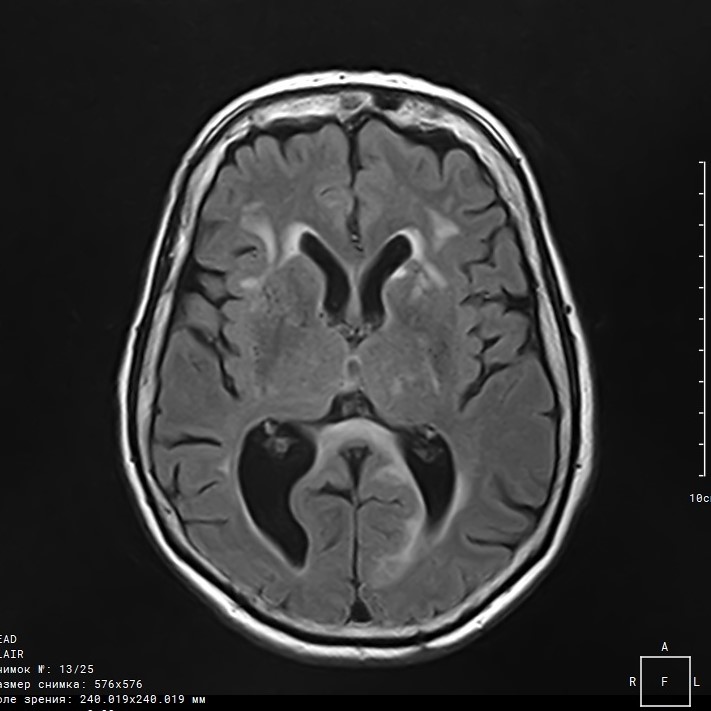

Острый период очень хорошо визуализируется на МРТ в отличие от КТ и позволяет определить тип и вид поражения головного мозга и провести дифференциальную диагностик ишемической патологии: гематомы, в результате разрыва аневризмы; кровоизлияния из АВМ; кровоизлияния в опухолевидный очаг. Признаками ишемического инсульта являются: снижение плотности ткани поврежденной области; повышенная интенсивность МР-сигнала в зоне ишемии; признаки повышенной отечности на вовлеченных участках (будет наблюдаться отек головного мозга, так как это является патологической реакцией головного мозга на токсические агенты, но в зоне вовлеченных участках отек будет больше).

Степень детекции геморрагических инсультов на МРТ тоже достаточно высока и позволяет выявить гематомы различной локализации. В крови содержится гемоглобин, который обладает определенными МР свойствами, а его сгустки очень хорошо визуализируются.